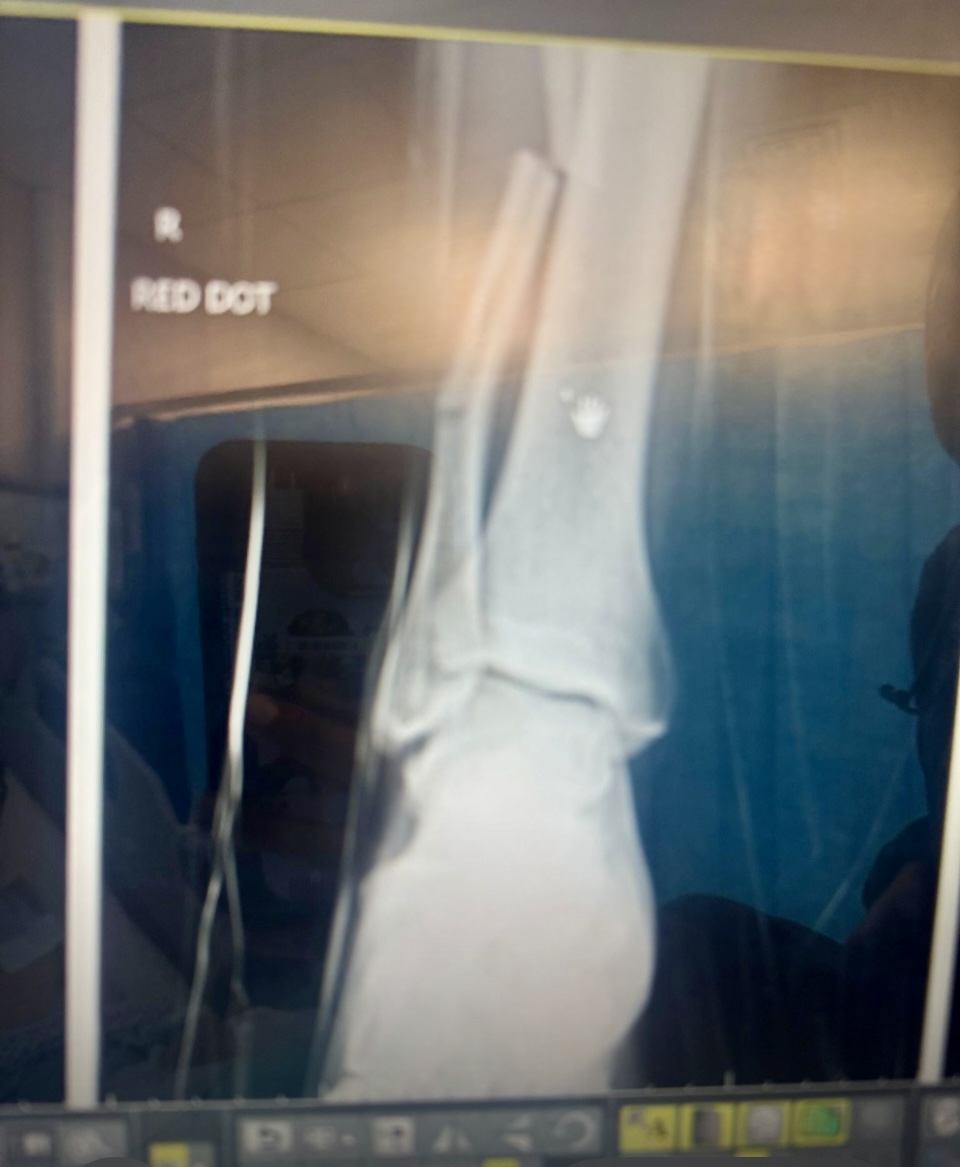

Emergency services, including both land and air ambulance teams, responded quickly, and Connor was transferred to hospital. There, he was diagnosed with five breaks to his tibia and fibula. He has since undergone surgery to repair the damage but is expected to remain incapacitated for several weeks, separated from his young family.